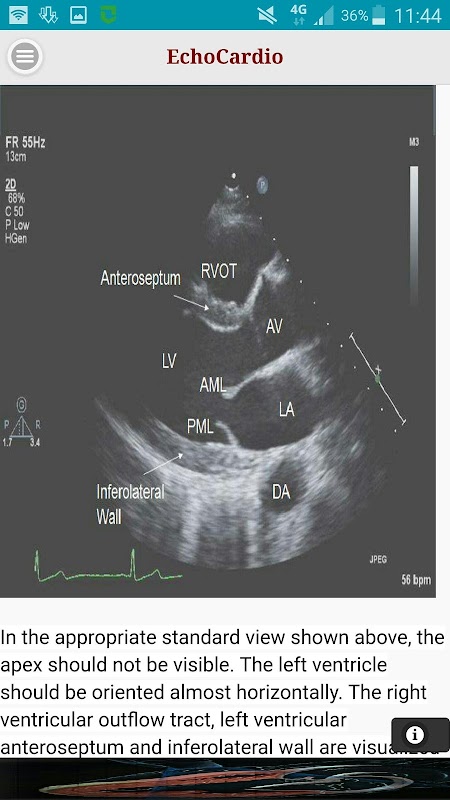

Трансторакальная эхокардиографии (TTE) является наиболее часто выполняется ультразвуковое обследование сердца. Трансторакальная эхокардиография высокого качества может быть выполнена быстро у постели больного и имеет потенциал, чтобы всесторонне оценить левого и правого желудочков систолического и диастолического функции, региональное движение стенки, клапанные пороки сердца и заболевания перикарда.

Парастернальная длинная ось